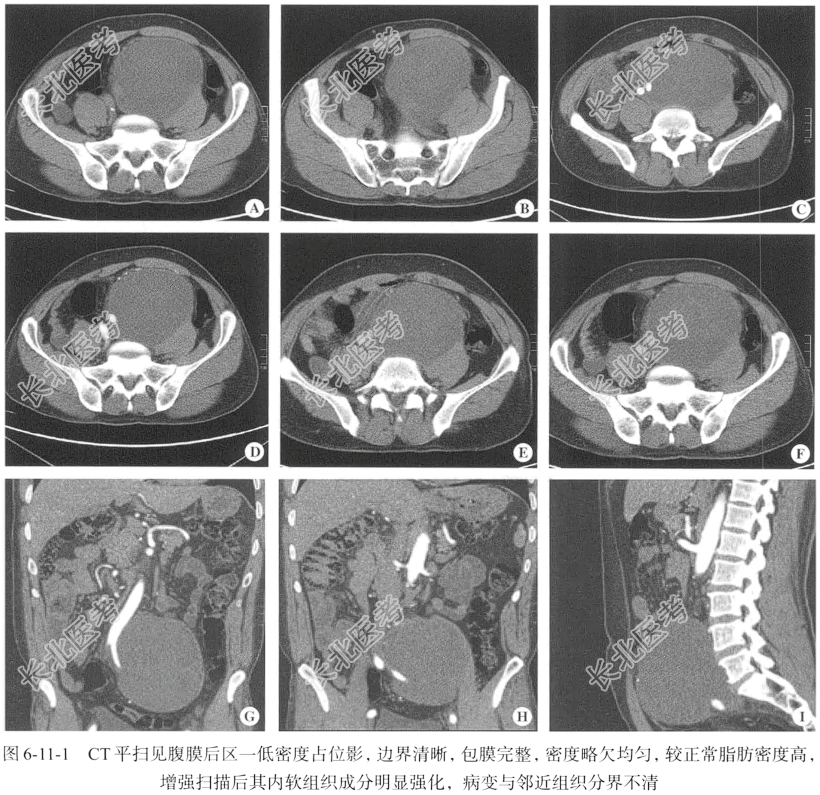

【影像图片】见图6-11-1。

【腹部CT检查】仰卧位,横断位CT平扫及增强扫描,扫描层厚为5mm;后处理图像层厚为1.25mm,重建冠状位、矢状位图像。

【手术所见】腹膜后见一巨大占位,呈球形,包膜完整,张力较大,目测直径为12~15cm,病灶邻近的血管、肠管及脂肪组织呈受压改变,病灶后方与左侧腰大肌分界不清,周围结构略紊乱,呈炎性渗出改变,切除病灶,包膜内见大量果冻样坏死组织,术中切除大部分瘤体,连同病灶包膜一并切除,送快速冰冻病理检查。

【病理诊断】黏液性脂肪肉瘤。